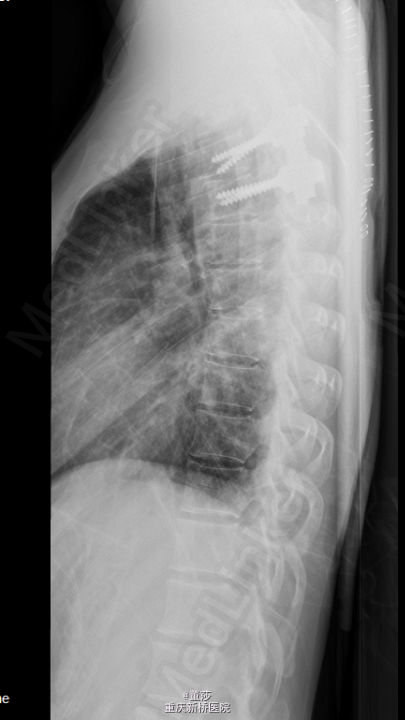

初步诊断:1.胸椎肿瘤:转移癌/肺恶性肿瘤。全身麻醉下行“胸椎恶性肿瘤后路肿瘤切除,椎管减压、内固定术”,术中予椎体内填充骨水泥,C5,C6,C7各打入一枚颈椎侧块螺钉,T3、T4两侧各打入一枚椎弓根螺钉,C臂机透视提示螺钉位置可。

术中冰冻:胸1,2椎肿瘤(2):显著增生的纤维结缔组织内有少量异型细胞,考虑转移性低分化腺癌。术后予锋替新2.0g ivgtt bid预防感染及镇痛,补液改善循环,促进愈合治疗等对症治疗。术后复查胸椎片:颈、胸椎后路术改变,术后内固定在位,胸1、2椎体内见高密度影。胸椎顺列。所见椎间隙无殊。